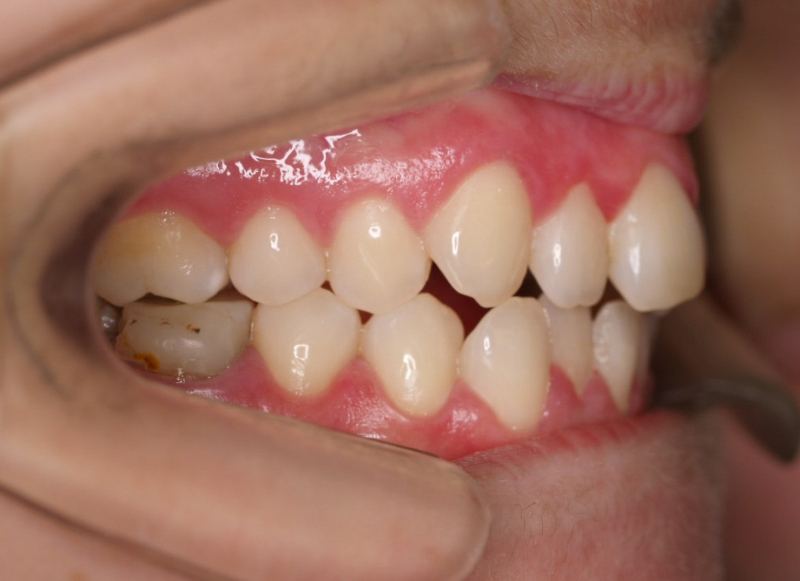

Premolar mandibular incluido + fenestración

45 incluido